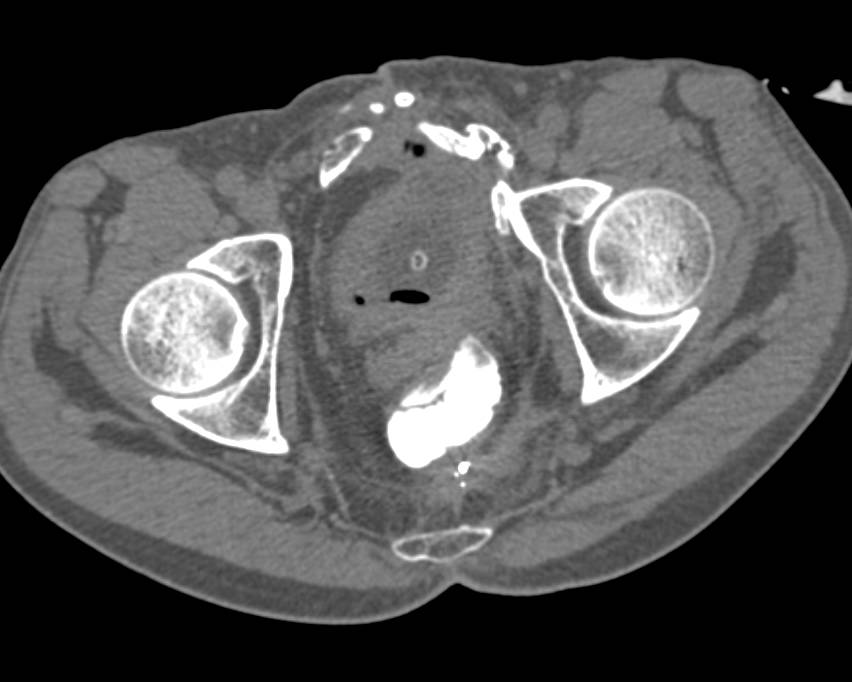

Emphysematous Cystitis